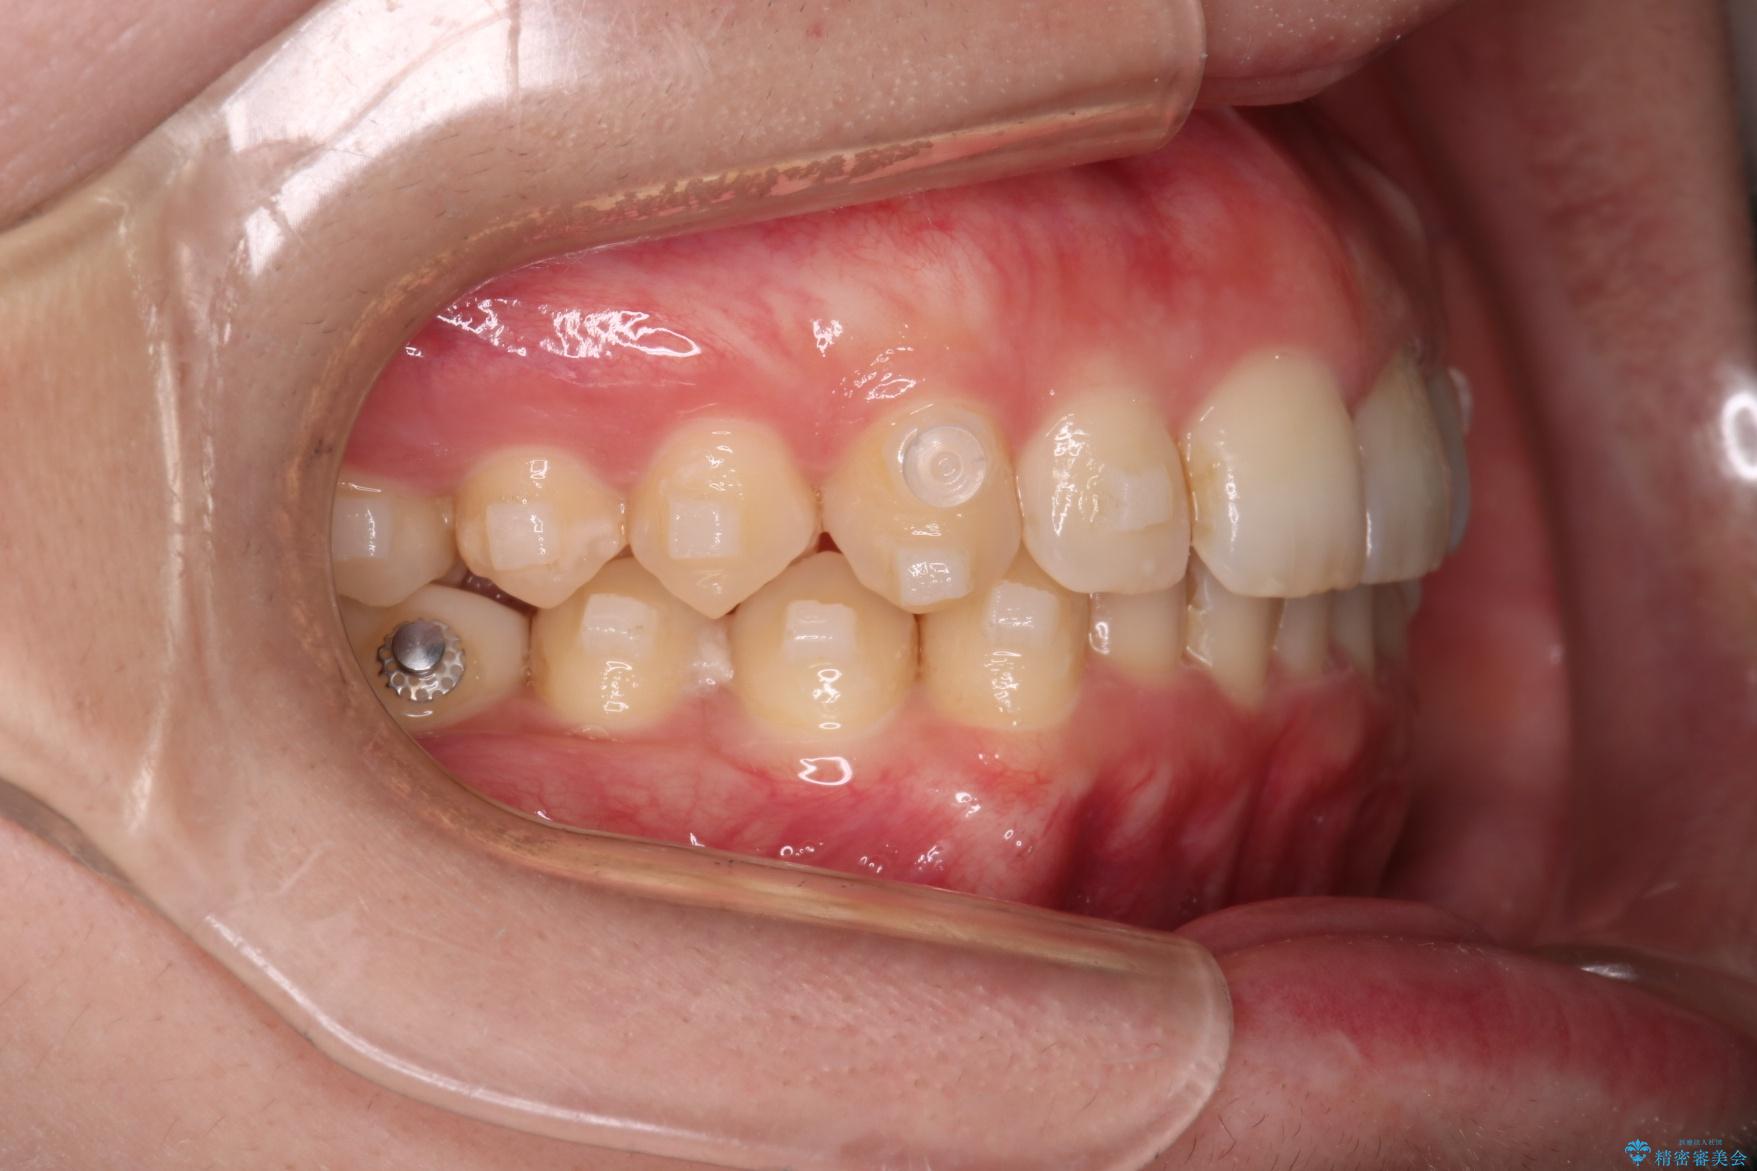

- インビザライン・ワイヤー装置(クリア装置)

- 下の歯のがたつきを主訴に来院されました。

下の歯のがたつきと右の奥歯の噛みあわせ改善するために治療計画を立てることにしました。

右側臼歯部の咬合改善のために、臼歯部のみ部分的なワイヤー矯正を行い、咬合改善がみられてからインビザラインにて全体的な矯正を行なっていく治療計画を立てました。

噛み合わせをよくするために、ワイヤー矯正とインビザライン矯正のどちらの期間も必要な箇所にゴム掛けを行いながら治療を行いました。

下の前歯のがたつき改善にはIPR(歯と歯の間を削る処置)を行いました。